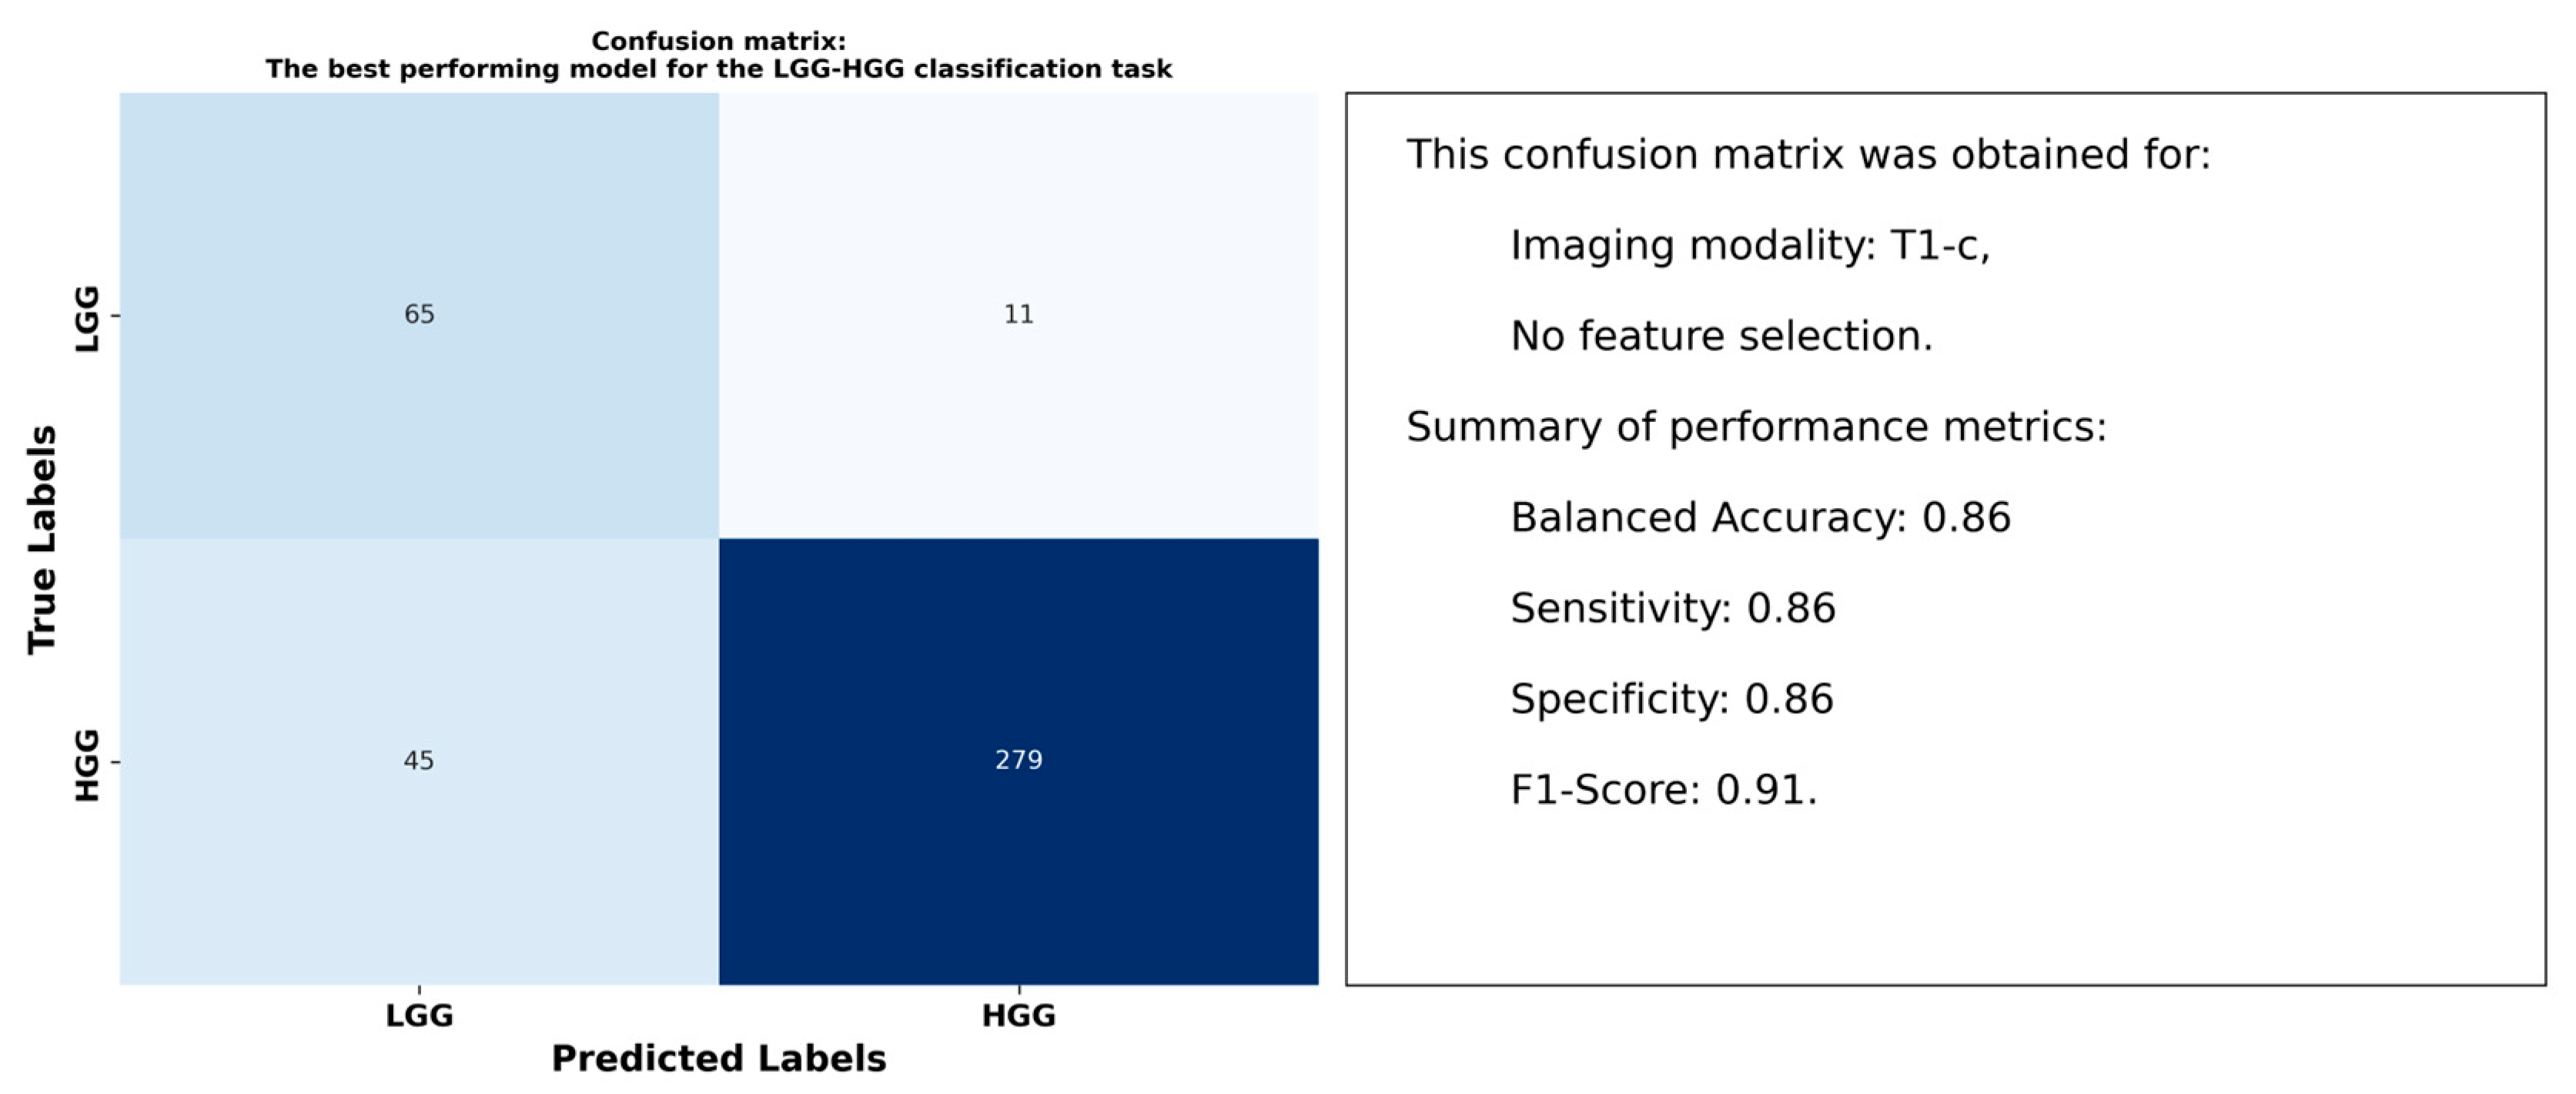

3.1. Results for the LGG-HGG Classification Task

4.2. Optimal Models and Superior Performance of T1-c Features